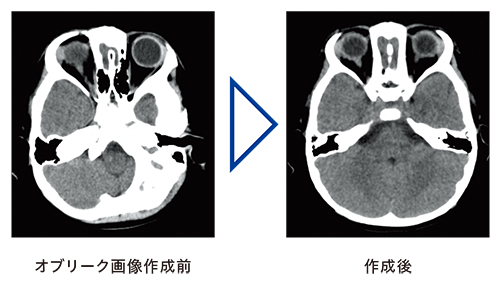

特長<3>

高精細・高画質を可能にする0.625mmサブミリ撮影

0.625mm×16chの撮影により,高精細な画像を短時間で撮影可能です。滑らかな3D画像,MPR画像も得られ,撮影後にはMPRによるオブリーク画像の作成も可能です。

ガントリチルトで高画質撮影

放射線感受性の高い部位への被ばく低減を目的に±30°の範囲でガントリチルトが可能です。頭部をノーマルスキャンで撮影することで,ボリュームスキャンよりも低コントラストの優れた高画質撮影が可能です。